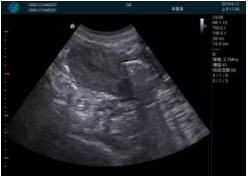

抽吸結(jié)束后縱切子宮,孕囊已被完全抽吸,未見明顯殘留

橫切子宮,發(fā)現(xiàn)右側(cè)宮腔靠近宮角處有少許脫模樣殘留

二次抽吸后再次進行超聲檢查,宮腔未見殘留,宮腔線清晰顯示